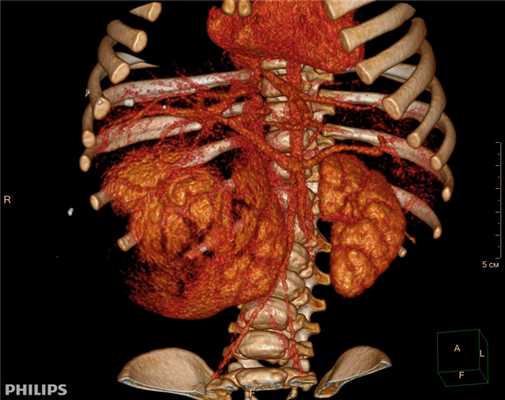

3D-реконструкции опухоли Вильмса пациентов детского отделения НМИЦ онкологии им. Н.Н. Петрова

Опухоль Вильмса. Компьютерная томография

Рисунок 1. КТ брюшной полости ребенка с большой нефробластомой с метастазами в печень.

Клинически: при пальпации опухоль в проекции правой почки до 12 см в диаметре. Общеклинические исследования в пределах возрастной нормы. При КТ органов брюшной и грудной полости: КТ-картина объемного образования правой почки без признаков интрапульмональных метастазов (см. рис. 2). УЗИ брюшной полости: в проекции правой почки солидно-кистозное образование 101ґ114ґ99 мм, объемом 500 мл, васкуляризация активная, интактная часть почки 57ґ12ґ40 мм. Объемное образование правой почки — опухоль Вильмса. Предварительный диагноз: опухоль Вильмса правой почки, 2-я стадия.

Ребенку проведена предоперационная химиотерапия. На 5-й неделе лечения КТ-контроль показал уменьшение опухоли в размерах до 90ґ80ґ100 мм (см. рис. 3).